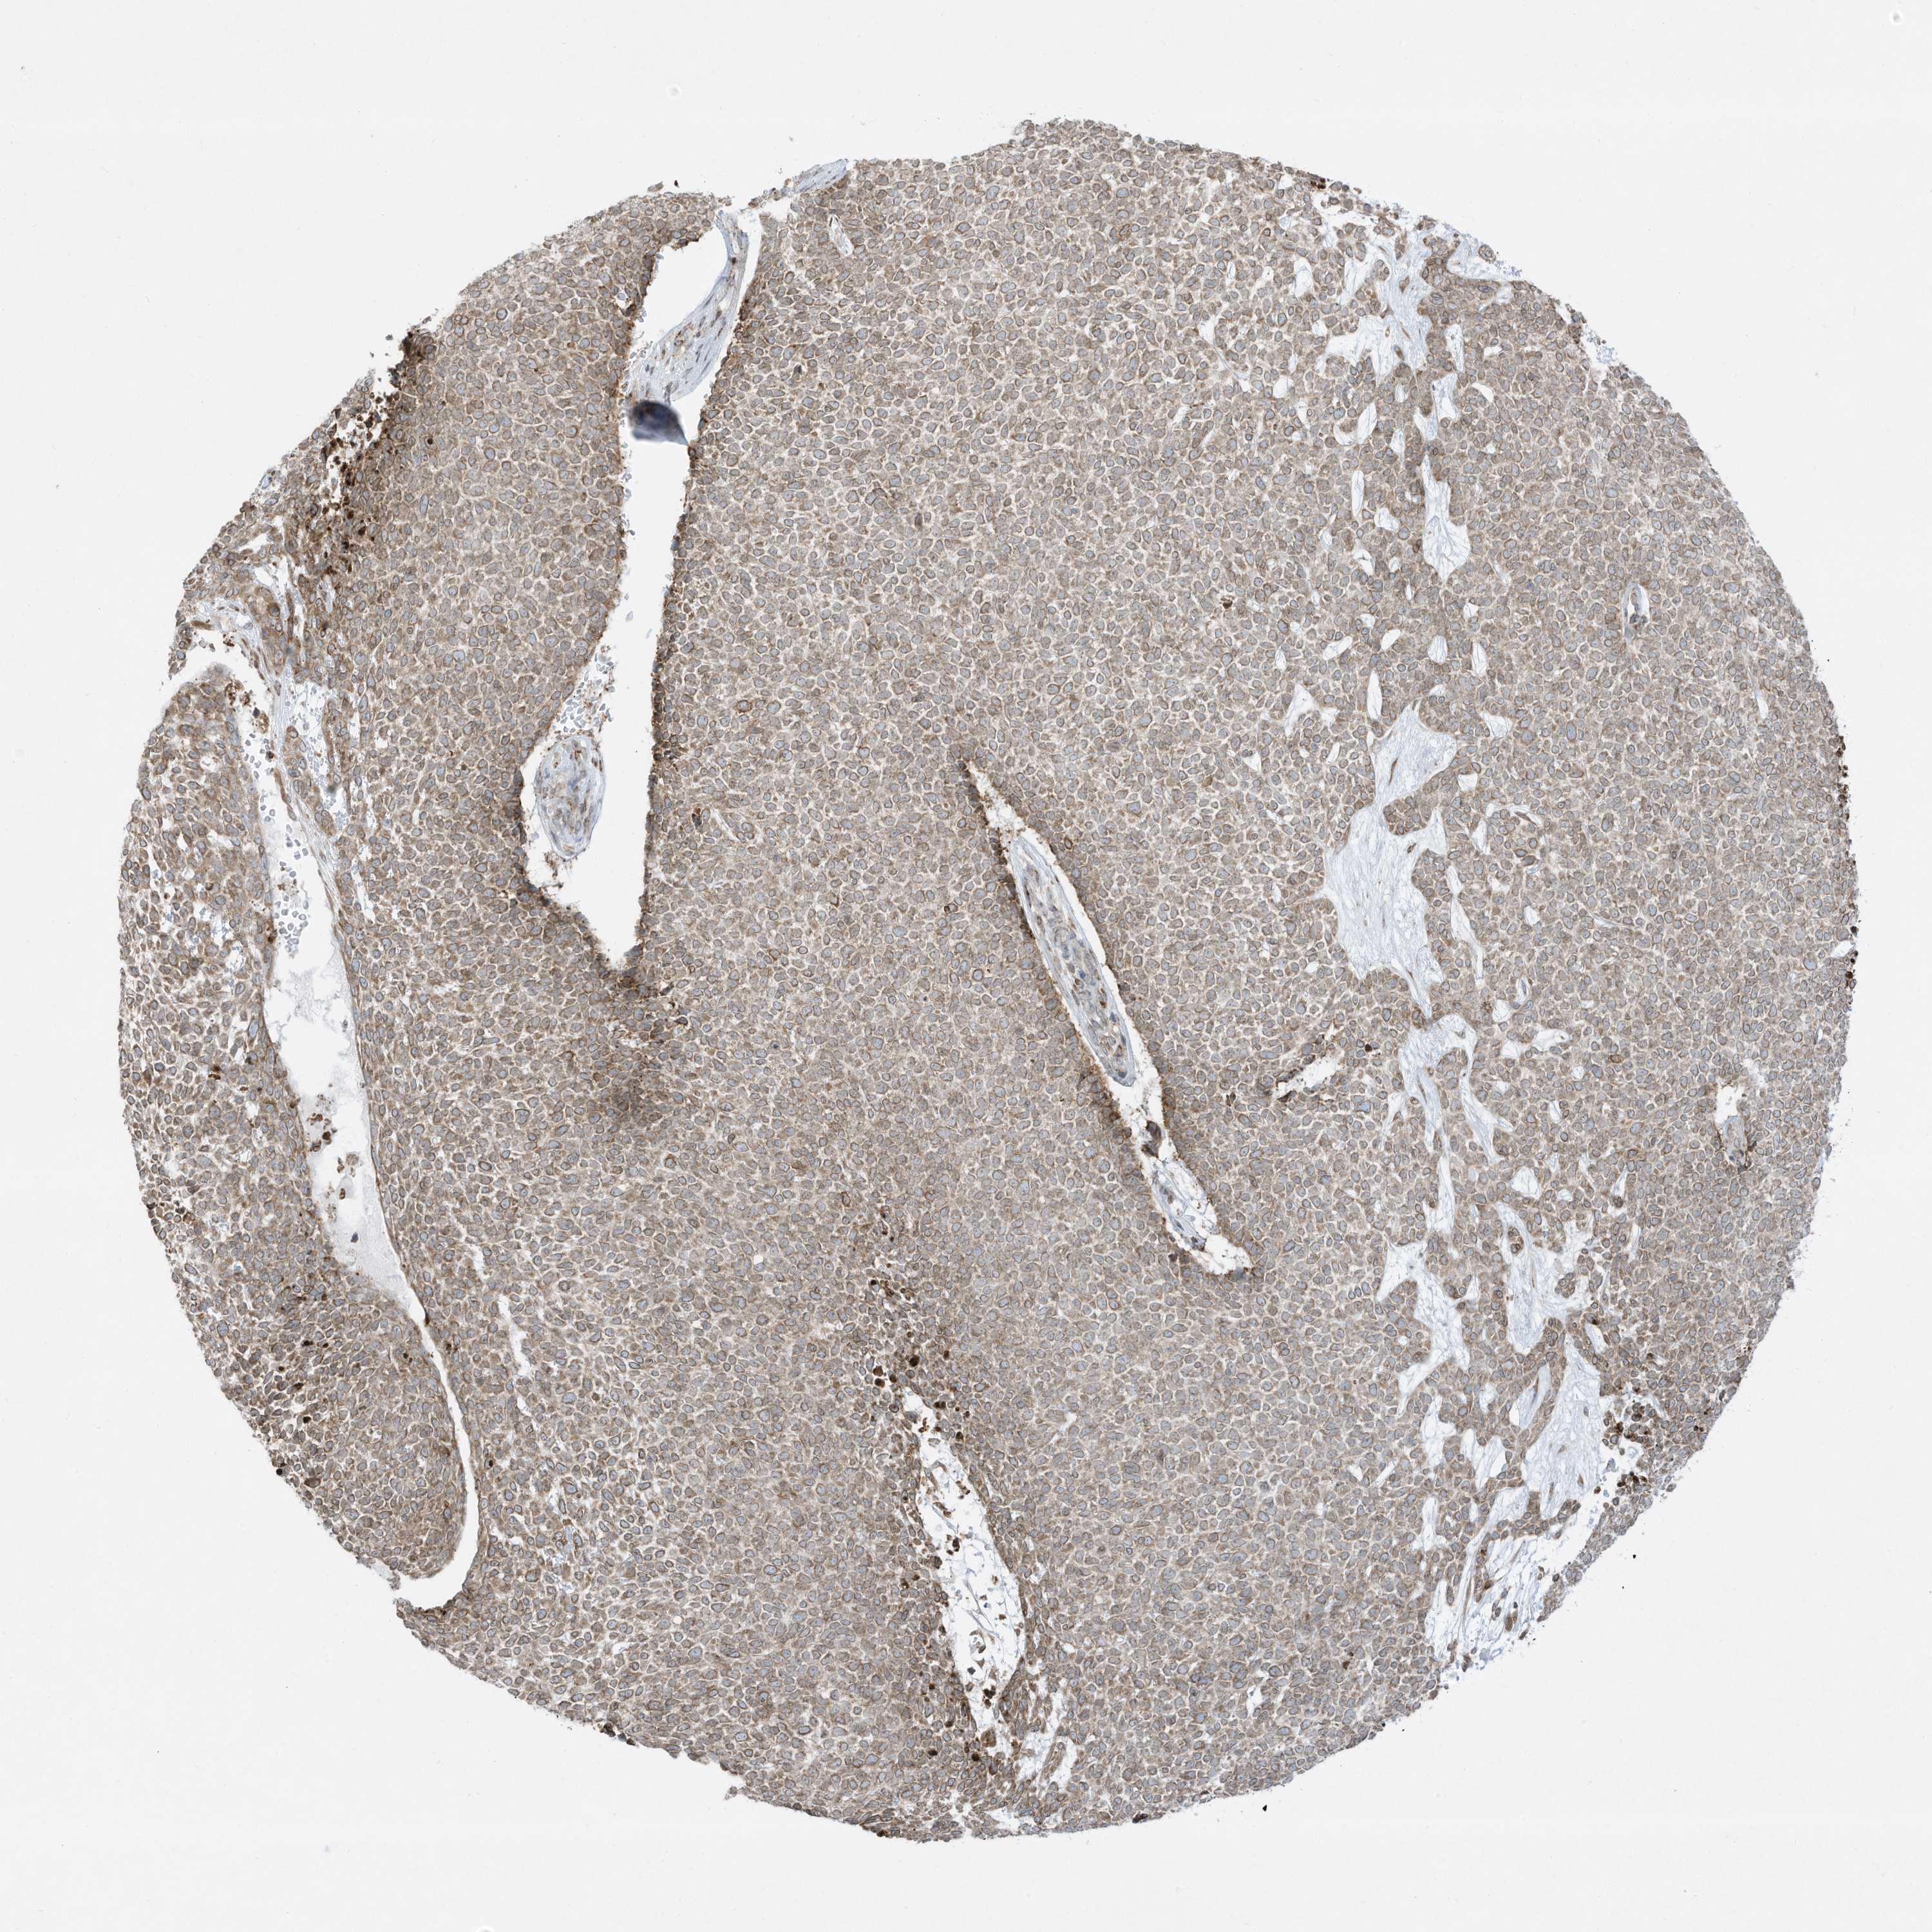

SKIN CANCER - Protein expressioni

A mouse-over function shows sample information and annotation data. Click on an image to view it in a full screen mode. Samples can be filtered based on level of antibody staining by selecting one or several of the following categories: high, medium, low and not detected. The assay and annotation is described here.

Each image is clickable and will lead to virtual microscopy that enables deeper exploration of all samples and also displays staining intensity scores, fraction scores and subcellular localization as well as patient and tissue information for each sample.

Antibody HPA036071

Squamous cell carcinoma, NOS